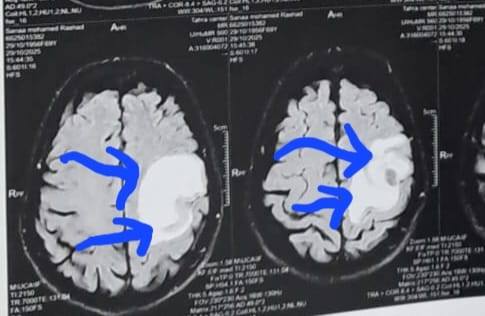

وكشف الدكتور إبراهيم الغريب رئيس قسم جراحة المخ والأعصاب بالمستشفى، أنه تعود تفاصيل الحالة إلى استقبال المستشفى المريضة بالعيادة الخارجية وهي تشكو من تنميل وضعف بالجانب الأيمن وثقل بسيط في الكلام، وبإجراء الفحوصات اللازمة من أشعة مقطعية ورنين مغناطيسي بالصبغة، تبين وجود ورم بالمخ، وتم إعطاؤها العلاج المناسب لحين استكمال الفحوصات.

وتابع "الغريب"، أنه مع تدهور حالتها الصحية، جرى التعامل مع الحالة بشكل عاجل، حيث تم تجهيز المريضة للجراحة، وحجز سرير بالعناية المركزة، وعمل عروض لكافة التخصصات، مع توفير الدم والبلازما واستكمال جميع التحاليل والفحوصات اللازمة، ودخلت المريضة غرفة العمليات، حيث أجريت جراحة مخ دقيقة شملت فتح عظام الجمجمة، وفصل الورم تدريجيا عن أنسجة المخ مع السيطرة على الأوعية الدموية المغذية له.

أشعة المريضة

الأشعة الخاصة بالمريضة

الأشعة